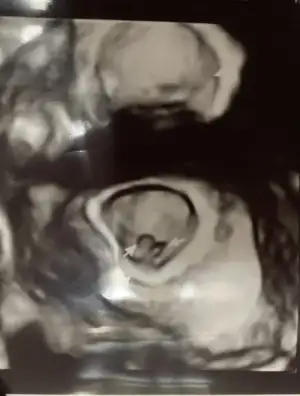

Evet kadın doğum doktoru baktı canım , damar genişlemesi olabilir. Belki bir yara vardı o kanama yapmış olabilir , Corasprin kaynaklı olabilir , üstüne görme olabilir dedi, ama alanda hiç bir kanama görmedi hatta bebişin gelişimi de 3gün ilerde imiş .